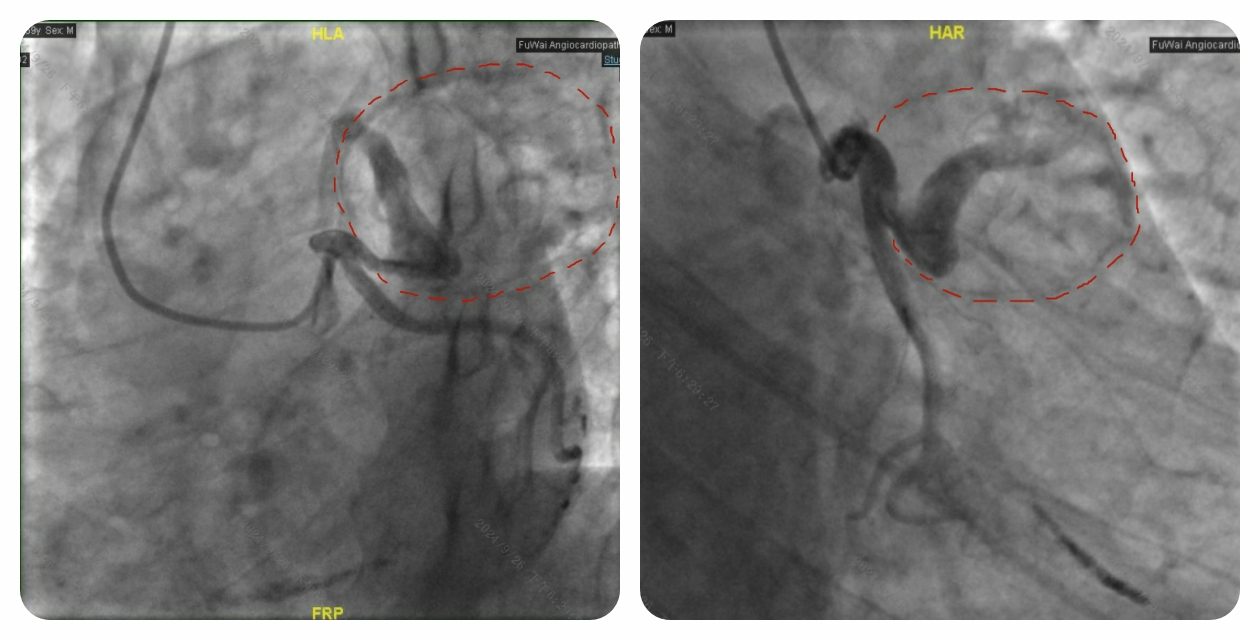

59 岁的老秦(化名),被高血压、高血脂困扰了 10 多年。因不明原因的心慌,他来到云南省阜外医院。入院前一个月左右,老秦时常感觉心慌得厉害,心慌时还伴有头晕症状,每次心慌持续几分钟后自行缓解,好在未曾出现胸口疼痛、晕厥等情况。鉴于老秦的年龄较大,我们为他安排了冠状动脉 CT 检查。这不查不知道,一查吓一跳,老秦的心脏表面竟冒出了一个 “大地雷”。仔细查看,这个 “大地雷” 紧紧包裹着左侧冠状动脉中最重要的血管 —— 前降支。更糟糕的是,“地雷” 内的血液已经凝固成血栓,表面还形成了一层钙化的 “铠甲”,仿佛一颗随时可能引爆的 “定时炸弹”。

为了确定是否需要为老秦实施外科手术 “排雷”,我们紧接着安排了冠状动脉造影检查。结果显示,虽然冠状动脉前降支被 “地雷” 包裹,但血管腔依旧通畅,“地雷” 没有对冠状动脉造成压迫,血管内的血液也没有渗漏到 “地雷” 内。

经过手术专家们的深入讨论,一致认定老秦心脏上的 “地雷” 属于冠状动脉假性动脉瘤。由于 “地雷” 没有压迫冠状动脉,血液没有外溢,且表面有 “铠甲” 保护,内部又是实心血栓,爆炸风险相对较低。综合考虑老秦的意见后,专家团队决定暂不进行外科 “排雷”,而是建议他定期复查,密切关注 “地雷” 的动态。